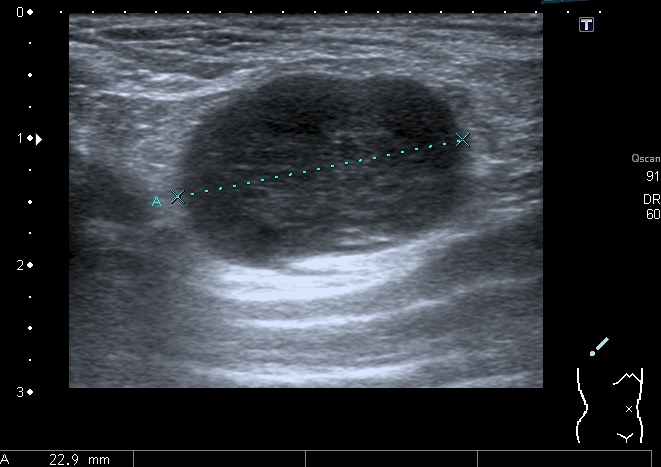

На УЗИ - такая картинка:

Деструкция корткального слоя 7-го ребра с ткаенвым компонетом, исходящим из кости. 7th rib destruction with solid mass

Поперечный скан. Transverse scan

образование оттесняет сосуд,  в самом кровоток достоверно не определяется. No bloodflow in mass is detected.